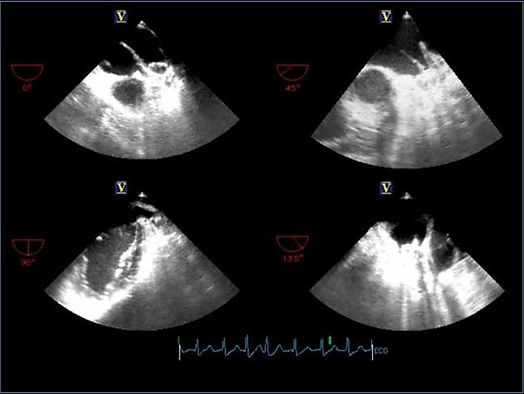

Cihazın implant prosedürü genellikle bir saat sürer ve hasta o günü hastanede geçirir. Hastaya genel anestezi altında transseptal tekniği kullanılarak kateterizasyon uygulaması gerçekleştirilir ve hangi boyutta Watchman cihazının yerleştirileceğini belirlemek için hastanın sol atriyal uzantısı ölçülür. Bunun için ise ekokardiyografi ve bu yöntemin yetersiz kaldığı durumlarda transözofageal ekokardiyogram (TEE) kullanılır. Bu gerekliliğe yol açan durumlar; kalpte pıhtı veya enfeksiyon varlığının araştırılması, yapay kapak işlevlerinin değerlendirilmesi, kalp kapak tamiri veya kalp kapaklarının kapatılması ameliyatları sırasında ve sonrasında ameliyatın başarı durumunu ölçmektir.Doğru boyutlarda cihaz seçildikten sonra Watchman kılıfı, femoral venden girilerek tel üzerinden sol atriyuma ilerletilir. Erişim kılıfı pigtail kateter üzerinden SAA’nın distal kısmına gönderilir. Dağıtım sistemi hazırlanıp erişim kılıfına yerleştirildikten sonra Watchman de SAA’ya yerleştirilir. Cihaz uygulamaya geçmeden önce son kez floroskopi ve TEE ile kontrol edilir. Son olarak cihaz açılır, böylece SAA kapanır ve hastalar operasyon sonunda antikoagülan almayı durdurup inme riskini azaltmış olurlar (1).

Hacettepe Üniversitesi Tıp Fakültesi Kardiyoloji Anabilim Dalı, Watchman cihazının etkinliğini değerlendirmek adına bir çalışma gerçekleştirdi. Oral antikoagülasyon tedavisi için kontrendikasyonu bulunan ve inme gerçekleşme olasılığı yüksek, 8’i erkek 3’ü kadın olan 11 hastaya Watchman cihazıyla perkütan yolla sol atriyal apandis kapatma işlemi uygulandı. Genel anestezi altında gerçekleştirilen işlem floroskopi ve TEE kılavuzluğunda yapıldı. Daha sonra hastalar 6 aylık bir kontrol sürecine girdi.Kontrollerde SAA’da trombüs oluşmadan cihazın kapandığı gözlemlendi. Yalnızca iki hastada cihaz çevresinde 3 milimetreden daha küçük olan kaçak belirlendi fakat bu kaçaklar hastalarda herhangi bir soruna neden olmadı. Sonuç olarak SAA kapatılmasında %100 oranında bir başarı elde edildi. Hacettepe Üniversitesi Tıp Fakültesinin çalışmalarının kısa dönem sonuçlarında, Watchman SAA sisteminin güvenilir ve uygulanabilir bir yöntem olduğu gösterildi.